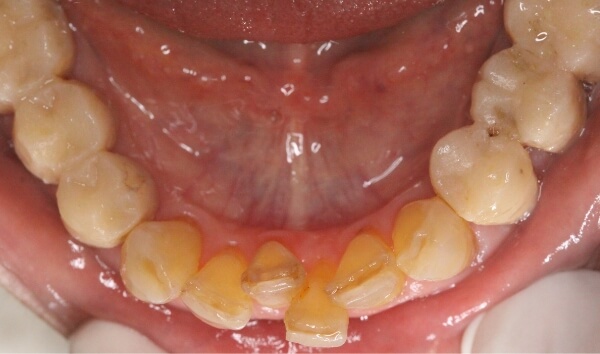

上下の前歯に、大きな隙間があります。

術前